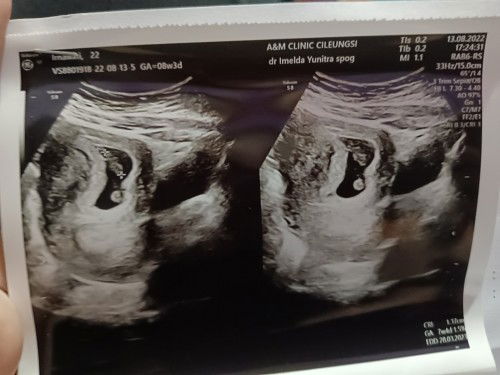

Usg 7 week

Bunda mau nanya ini udh keliatan janin nya kan ya katanya usia janin 7week suruh blik lgi buln bsk katanya saya jadi was2 takut 😟